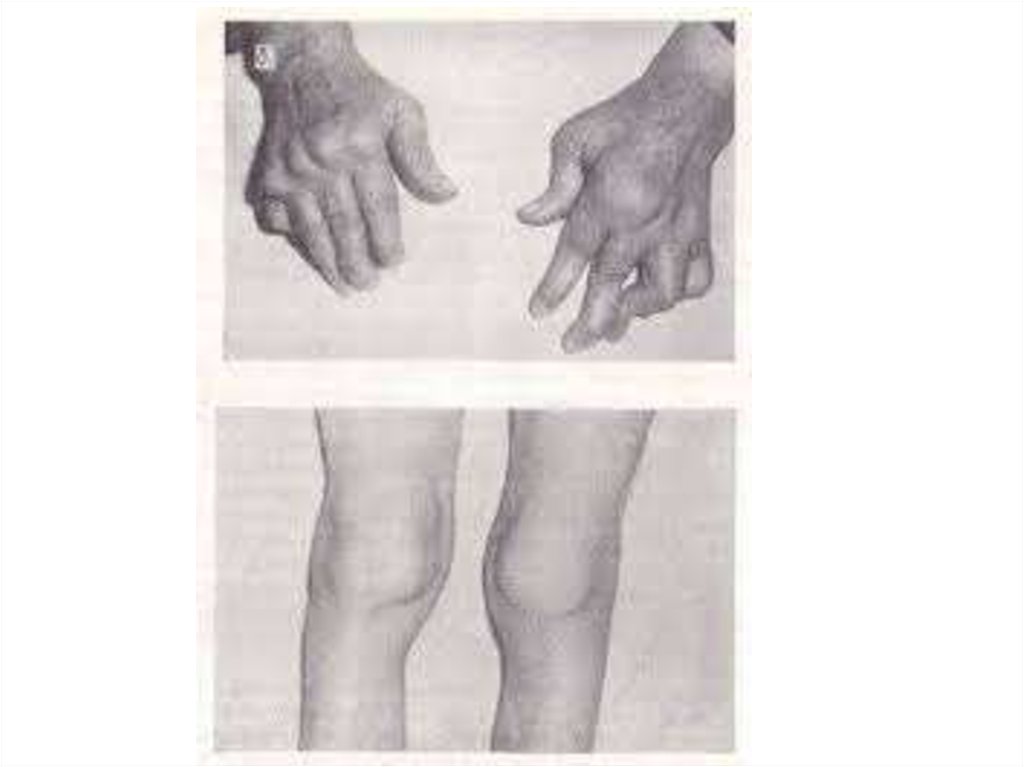

Медицинские аспекты заболеваний: рентгенологическая картина туберкулеза костей

Раздел: Снимки-откровения